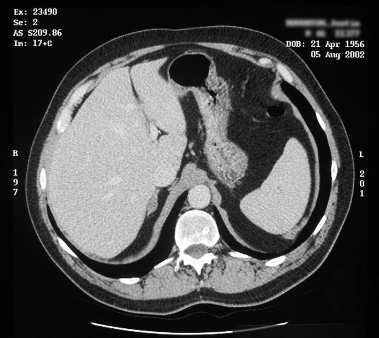

Tomografia computadorizada (TC) mostrando lesão na glândula adrenal direita em paciente com hiperplasia adrenal bilateral

Do acervo pessoal do Dr. Michael Stowasser; usado com permissão